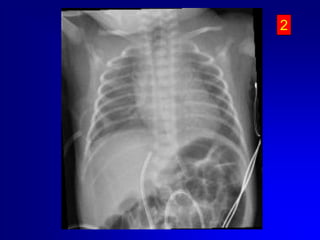

Eseguire sempre controllo radiografico o ecografico della posizione del catetere..

Eseguire semprecontrollo radiografico o ecografico della posizione del catetere..